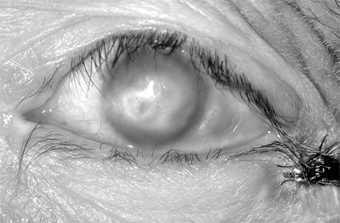

Figure 5-8: Acute hemorrhagic conjunctivitis. The virus is transmitted by close person-to-person contact and by such fomites as common linens, contaminated optical instruments, and water. Recovery occurs within 5-7 days, and there is no known treatment. In the USA, closing of schools has been done to stop epidemics. 2. CHRONIC VIRAL CONJUNCTIVITIS Molluscum Contagiosum Blepharoconjunctivitis A molluscum nodule on the lid margins or the skin of the lids or brow may produce unilateral chronic follicular conjunctivitis, superior keratitis, and superior pannus and may resemble trachoma. The inflammatory reaction is predominantly mononuclear (unlike the reaction in trachoma), and the round, waxy, pearly-white, noninflammatory lesion with an umbilicated center is typical of molluscum contagiosum (Figure 5-9). Biopsy shows eosinophilic cytoplasmic inclusions that fill the entire cytoplasm of the enlarged cell, pushing its nucleus to one side.

Figure 5-9: Molluscum contagiosum of lid margin. Follicular conjunctivitis was present. Excision, simple incision of the nodule to allow peripheral blood to permeate it, or cryotherapy cures the conjunctivitis. On very rare occasions (reports of only two cases have appeared in the literature), molluscum nodules have occurred on the conjunctiva. In these cases, excision of the nodule has also relieved the conjunctivitis. Multiple lid or facial lesions of molluscum contagiosum have been seen in patients with acquired immune deficiency syndrome (AIDS). Varicella-Zoster Blepharoconjunctivitis Hyperemia and an infiltrative conjunctivitis-associated with the typical vesicular eruption along the dermatomal distribution of the ophthalmic branch of the trigeminal nerve-are characteristic of herpes zoster (preferably called simply zoster). The conjunctivitis is usually papillary, but follicles, pseudomembranes, and transitory vesicles that later ulcerate have all been noted. A tender preauricular lymph node occurs early in the disease. Scarring of the lid, entropion, and the misdirection of individual lashes are sequelae. The lid lesions of varicella, which are like the skin lesions (pox) elsewhere, may appear on both the lid margins and the lids and often leave scars. A mild exudative conjunctivitis often occurs, but discrete conjunctival lesions (except at the limbus) are very rare. Limbal lesions resemble phlyctenules and may go through all the stages of vesicle, papule, and ulcer. The adjacent cornea becomes infiltrated and may vascularize. In both zoster and varicella, scrapings from lid vesicles contain giant cells and a predominance of polymorphonuclear leukocytes; scrapings from the conjunctiva in varicella and from conjunctival vesicles in zoster may contain giant cells and monocytes. The virus can be recovered in tissue cultures of human embryo cells. Oral acyclovir in high doses (800 mg orally five times daily for 10 days), if given early in the course of the disease, appears to limit the severity of the illness. Measles Keratoconjunctivitis The characteristic enanthem of measles frequently precedes the skin eruption. At this early stage, the conjunctiva may have a peculiar glassy appearance, followed within a few days by swelling of the semilunar fold (Meyer's sign). Several days before the skin eruption, an exudative conjunctivitis with a mucopurulent discharge develops, and at the time of the skin eruption, Koplik's spots appear on the conjunctiva and occasionally on the caruncle. At some time (early in children, late in adults), epithelial keratitis supervenes. In the immunocompetent patient, measles keratoconjunctivitis has few or no sequelae, but in malnourished or otherwise immunoincompetent patients the ocular disease is frequently associated with a secondary HSV or bacterial infection due to S pneumoniae, H influenzae, and other organisms. These agents may lead to purulent conjunctivitis with associated corneal ulceration and severe visual loss. Herpes infection can cause severe corneal ulceration with corneal perforation and loss of vision in poorly nourished children in developing countries. Conjunctival scrapings show a mononuclear cell reaction unless there are pseudomembranes or secondary infection. Giemsa-stained preparations contain giant cells. Since there is no specific therapy, only supportive measures are indicated unless there is secondary infection. RICKETTSIAL CONJUNCTIVITIS All rickettsiae recognized as pathogenic for humans may attack the conjunctiva, and the conjunctiva may be their portal of entry. Q fever is associated with severe conjunctival hyperemia. Treatment with systemic tetracycline or chloramphenicol is curative. Marseilles fever (boutonneuse fever) is often associated with ulcerative or granulomatous conjunctivitis and a grossly visible preauricular lymph node. Endemic (murine) typhus, scrub typhus, Rocky Mountain spotted fever, and epidemic typhus have associated, variable, and usually mild conjunctival signs. FUNGAL CONJUNCTIVITIS Candidal Conjunctivitis Conjunctivitis caused by Candida species (usually Candida albicans) is a rare infection that usually appears as a white plaque. This may occur in diabetics or immunocompromised patients as an ulcerative or granulomatous conjunctivitis. Scrapings show a polymorphonuclear cell inflammatory reaction. The organism grows readily on blood agar or Sabouraud's medium and can be readily identified as a budding yeast or, rarely, as pseudohyphae. The infection responds to amphotericin B (3-8 mg/mL) in aqueous (not saline) solution or to applications of nystatin dermatologic cream (100,000 units/g) four to six times daily. The ointment must be applied carefully to be sure that it reaches the conjunctival sac and does not just build up on the lid margins. Other Fungal Conjunctivitides Sporothrix schenckii may rarely involve the conjunctiva or the eyelids. It is a granulomatous disease associated with a visible preauricular node. Microscopic examination of a biopsy of the granuloma reveals gram-positive, cigar-shaped conidia (spores). Rhinosporidium seeberi may rarely affect the conjunctiva, lacrimal sac, lids, canaliculi, and sclera. The typical lesion is a polypoid granuloma that bleeds after minimal trauma. Histologic examination shows a granuloma with enclosed large spherules containing myriads of endospores. Treatment is by simple excision and cauterization of the base. Coccidioides immitis may rarely cause a granulomatous conjunctivitis associated with a grossly visible preauricular node (Parinaud's oculoglandular syndrome). This is not a primary disease but a manifestation of metastatic infection from a primary pulmonary infection (San Joaquin Valley fever). Disseminated disease suggests a poor prognosis. PARASITIC CONJUNCTIVITIS* Thelazia californiensis Infection The natural habitat of this roundworm is the eye of the dog, but it can also infect the eyes of cats, sheep, black bears, horses, and deer. Accidental infection of the human conjunctival sac has occurred. The disease can be treated effectively by removing the worms from the conjunctival sac with forceps or a cotton-tipped applicator. Loa loa Infection L loa is the eye worm of Africa. It lives in the connective tissue of humans and monkeys, and the monkey may be its reservoir. The parasite is transmitted by the bite of the horse or mango fly. The mature worm may then migrate to the lid, the conjunctiva, or the orbit. Infection with L loa is accompanied by a 60-80% eosinophilia, but diagnosis is made by identifying the worm on removal or by finding microfilariae in blood examined at midday. Diethylcarbamazine is currently the drug of choice. Ivermectin is being evaluated. Ascaris lumbricoides Infection (Butcher's Conjunctivitis) Ascaris may cause a rare type of violent conjunctivitis. When butchers or persons performing postmortem examinations cut tissue containing Ascaris, the tissue juice of some of the organisms may hit them in the eye. This can be followed by a violent and painful toxic conjunctivitis marked by extreme chemosis and lid edema. Treatment consists of rapid and thorough irrigation of the conjunctival sac. Trichinella spiralis Infection This parasite does not cause a true conjunctivitis, but in the course of its general dissemination there may be a doughy edema of the upper and lower eyelids, and over 50% of patients have chemosis-a pale, lemon-yellow swelling most marked over the lateral and medial rectus muscles and fading toward the limbus. The chemosis may last a week or more, and there is often pain on movement of the eyes. Schistosoma haematobium Infection Schistosomiasis (bilharziasis) is endemic in Egypt, especially in the region irrigated by the Nile. Granulomatous conjunctival lesions appearing as small, soft, smooth, pinkish-yellow tumors occur, especially in males. The symptoms are minimal. Diagnosis depends on microscopic examination of biopsy material, which shows a granuloma containing lymphocytes, plasma cells, giant cells, and eosinophils surrounding bilharzial ova in various stages of disintegration. Treatment consists of excision of the conjunctival granuloma and systemic therapy with antimonials such as niridazole. Taenia solium Infection This parasite rarely causes conjunctivitis but more often invades the retina, choroid, or vitreous to produce ocular cysticercosis. As a rule, the affected conjunctiva shows a subconjunctival cyst in the form of a localized hemispherical swelling, usually at the inner angle of the lower fornix, which is adherent to the underlying sclera and painful on pressure. The conjunctiva and lid may be inflamed and edematous. Diagnosis is based on a positive complement fixation or precipitin test or on demonstration of the organism in the gastrointestinal tract. Eosinophilia is a constant feature. The best treatment is to excise the lesion. The intestinal condition can be treated by niclosamide. Pthirus pubis Infection (Pubic Louse Infection) P pubis may infest the cilia and margins of the eyelids. Because of its size, the pubic louse seems to require widely spaced hair. For this reason it has a predilection for the widely spaced cilia as well as for pubic hair. The parasites apparently release an irritating substance (probably feces) that produces a toxic follicular conjunctivitis in children and an irritating papillary conjunctivitis in adults. The lid margin is usually red, and the patient may complain of intense itching. Finding the adult organism or the ova-shaped nits cemented to the eyelashes is diagnostic. Lindane (Kwell) 1% or RID (pyrethrins), applied to the pubic area and lash margins after removal of the nits, is usually curative. Application of lindane or RID to the lid margins must be undertaken with great care to avoid contact with the eye. Any ointment applied to the lid margin tends to smother the adult organisms. The patient's family and close contacts should be examined and treated. All clothes and fomites should be washed. Ophthalmomyiasis Myiasis is infection with larvae of flies. Many different species of flies may produce myiasis. The ocular tissues may be injured by mechanical transmission of disease-producing organisms and by the parasitic activities of the larvae in the ocular tissues. The larvae are able to invade either necrotic or healthy tissue. Many become infected by accidental ingestion of the eggs or larvae or by contamination of external wounds or skin. Infants and young children, alcoholics, and debilitated unattended patients are common targets for infection with myiasis-producing flies. These larvae may affect the ocular surface, the intraocular tissues, or the deeper orbital tissues. Ocular surface involvement may be caused by Musca domestica, the housefly, Fannia, the latrine fly, and Oestrus ovis, the sheep botfly. These flies deposit their eggs at the lower lid margin or inner canthus, and the larvae may remain on the surface of the eye, causing irritation, pain, and conjunctival hyperemia. Treatment of ocular surface myiasis is by mechanical removal of the larvae after topical anesthesia. ** Onchocerciasis is discussed in Chapter 7 PREVIOUS | NEXT Page: 1 | 2 | 3 | 4 | 5 | 6 | 7 | 8 | 9 | 10 | 11 | 12 | 13 | 14 10.1036/1535-8860.ch5 |